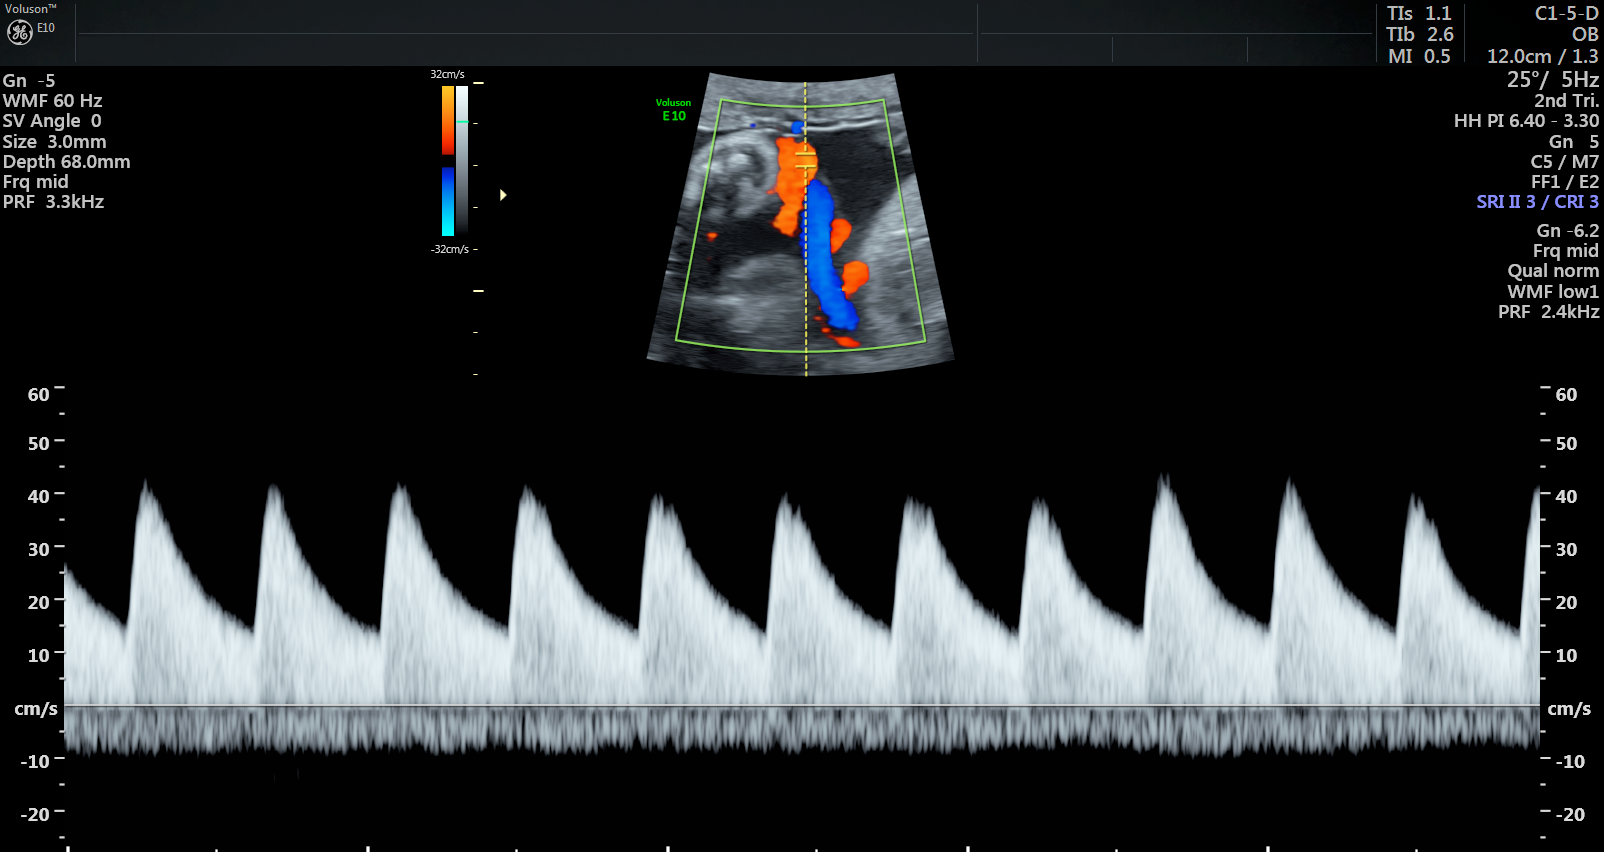

Currently, standard-of-care ultrasound scans measure blood flow at one point in the umbilical cord. The technique developed by Sled and his collaborators takes two measurements – one at the fetal end of the umbilical cord and one at the placental end. Sled says recording both measurements gives a much more accurate picture of the way blood is travelling through the umbilical cord.

“By looking at both measurements and the physics of how blood travels, we can get insight into how some of the finest blood vessels in the placenta are organized. The information this can provide to physicians is invaluable,” says Sled, who is also the Director of the Mouse Imaging Centre and a Professor and Vice-Chair in the Department of Medical Biophysics at the University of Toronto.

Animation showing where the new ultrasound technique measures blood flow along the umbilical cord. One measurement is taken at the fetal end and one is taken at the placental end.

The placenta has two blood circulations, one attached to the mother and another attached to the fetus. If the disease is primarily affecting the maternal circulation, it’s called maternal vascular malperfusion (MVM) and if the fetal circulation is primarily affected, it’s called fetal vascular malperfusion (FVM). MVM is the most common placental disease associated with fetal growth restriction, where a fetus is smaller than expected, and is often the cause of preventable stillbirth. FVM is less common but also associated with fetal growth restriction and other adverse outcomes.